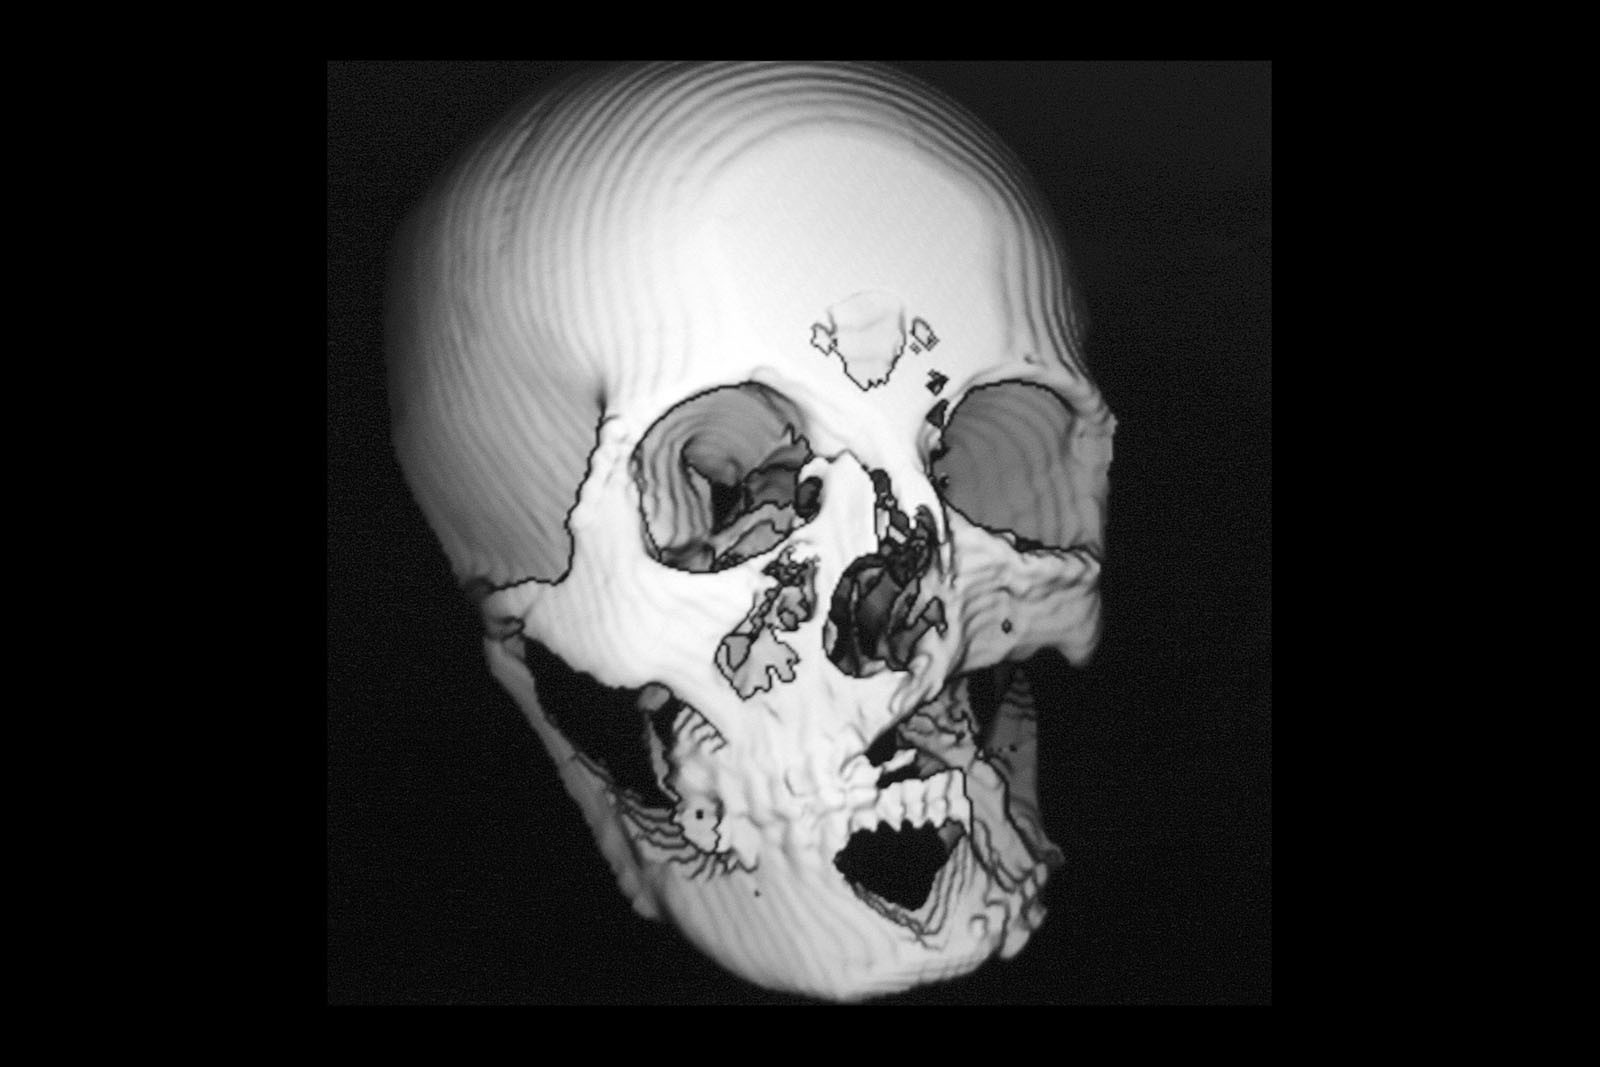

Narząd żucia stanowi funkcjonalną jedność z całym organizmem i nazywany jest układem stomatognatycznym. Zęby są jedynie częścią tego układu, w skład którego wchodzą kości twarzoczaszki, tkanki miękkie oraz układ nerwowo-naczyniowy.

Metoda Gerbera jako punkt wyjścia dla analizy traktuje staw skroniowo-żuchwowy. W relacji do jego funkcji bierze pod uwagę pozostałe ogniwa układu stomatognatycznego. Staw skroniowo-żuchwowy jest działającym synchronicznie symetrycznym elementem anatomii twarzoczaszki, który pozwala na otwieranie ust i funkcje z tym związane. To staw o złożonej budowie, w jego skład wchodzą: dołek stawowy kości skroniowej, który stanowi panewkę stawową, wyrostek kłykciowy, krążek stawowy i torebka stawowa. Krążek zbudowany jest z chrząstki i dzieli jamę stawową na dwie części: górną i dolną. Podczas ruchów opuszczania żuchwy (otwierania ust) krążek stawowy przesuwa się do przodu i dołu. Wraz z krążkiem przesuwa się wyrostek kłykciowy głowy żuchwy po obu stronach. W ruchu przywodzenia żuchwy (zamykania ust) krążek stawowy i wyrostek kłykciowy żuchwy wracają na swoje miejsce do pozycji wyjściowej. Stawy są sprzężone ze sobą czynnościowo (ruch następuje równocześnie w obu stawach) i anatomicznie (łączy je trzon kości żuchwy), stąd też nieprawidłowe asymetryczne obciążenia stawów są najczęstszą z przyczyn zaburzeń narządu żucia.

W ocenie wewnątrzstawowych patologii pomocna jest diagnostyka obrazowa. Konwencjonalne zdjęcia radiologiczne OPG, tomografia komputerowa oraz stożkowa tomografia komputerowa CBCT pozwalają na ocenę elementów kostnych stawu skroniowo-żuchwowego. Ocenę tkanek miękkich zlokalizowanych wewnątrzstawowo umożliwia rezonans magnetyczny NMR.